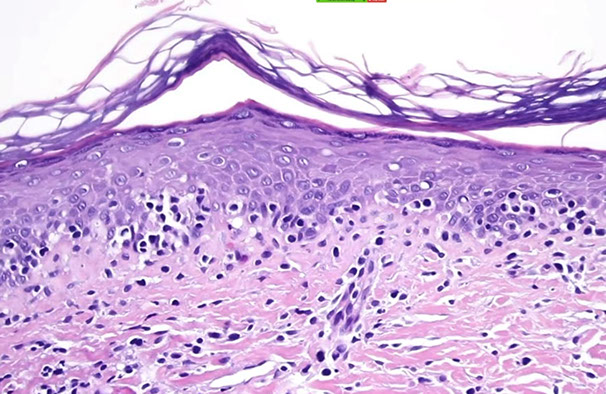

Cutaneous lymphoid hyperplasia in a 72-year-old man who presented with several purple-brown plaques on his cheeks and temples. A, The nodular infiltrate extends through the dermis with sparring of the overlying epidermis. B, It is characterized by scattered follicles with well-defined, reactive-appearing germinal centers, some of which have surrounding mantle zones. Many CD20-positive B cells are in the reactive follicles (C), and more numerous CD3-positive small T cells are present in the interfollicular areas (D). B-cell clonality studies (not shown) were negative for a clonal IGH or IGK gene rearrangement. [19]